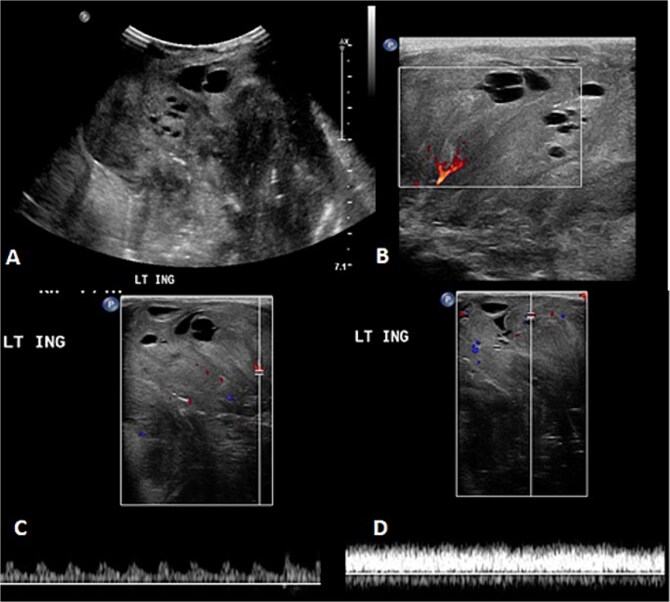

婴儿血管瘤(his)是最常见的婴儿肿瘤。它们是良性的,通常对心得安有反应。IHs很难与恶性软组织肿瘤如肉瘤区分。肉瘤是一种罕见的间充质肿瘤,类似于血管瘤,延迟治疗并影响预后。我们报告两例女婴的肉瘤最初被误诊为血管瘤。在第一个病例中,对1个月大的左腹股沟肿块患者使用丙泊洛尔。影像学显示为血管瘤。肿瘤生长需要活检,发现是肉瘤。在第二个病例中,一个2个月大的婴儿表现为快速增长和溃疡性左手肿胀,并被误诊为血管瘤。影像学和活检显示转移性肉瘤。两名患者都发生了脑转移并去世。这些病例强调,当遇到快速生长或溃疡时,需要重新评估his。早期发现对于获得最佳结果至关重要。

Infantile hemangiomas (IHs) are the most common infantile tumors. They are benign and often responsive to propranolol. IHs are difficult to distinguish from malignant soft tissue tumors like sarcomas. Sarcomas are rare mesenchymal tumors that mimic hemangiomas, delaying treatment and affecting outcomes. We report two instances in which female infants with sarcomas were initially misdiagnosed as hemangiomas. In the first case, propanolol was administered to a 1-month-old presenting with a left inguinal mass. Imaging revealed a hemangioma. Tumor growth necessitated a biopsy, revealing a sarcoma. In the second case, a 2-month-old presented with a rapid growing and ulcerating left-hand swelling and was misdiagnosed as a hemangioma. Imaging and biopsy revealed metastatic sarcoma. Both patients developed brain metastases and passed away. These cases highlight that IHs need to be re-evaluated when rapid growth or ulceration is encountered. Early detection is essential for optimal outcomes.